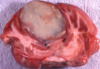

Name the pathologic process.

Hydrocephalus

Name the pathologic process.

Hydrocephalus

Name the pathologic process.

Hydrocephalus